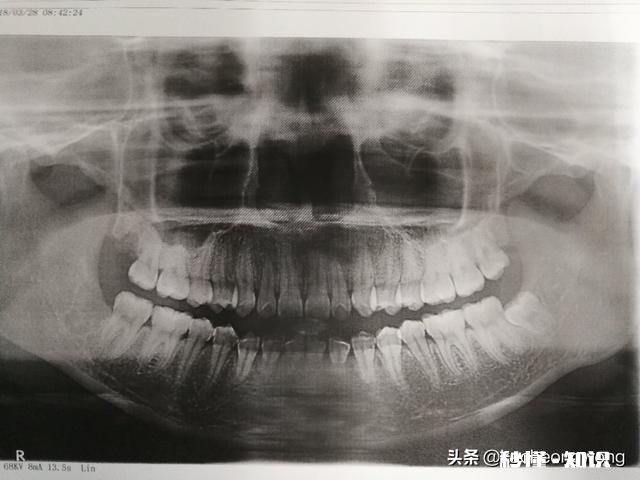

【智齿离神经多远】你看到这两个图右下角部位是患者左侧的智齿,这就距离神经管比较近,但具体是多少就要拍CT,因为这个全景X片是把颌骨曲面变成平面,所以会有重叠错位,你看到神经管在牙根之间其实很可能并没有,具体还是得看CT 。